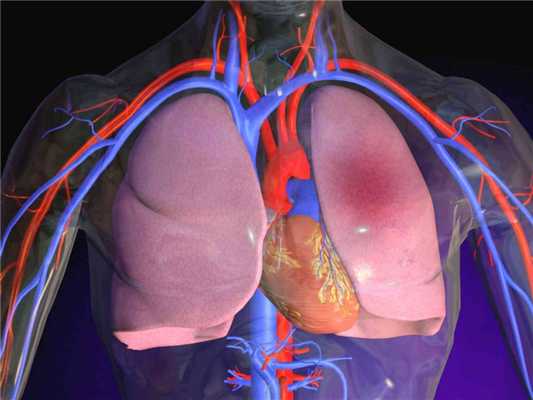

Рак легкого - это злокачественная опухоль, источником которой являются клетки бронхиального и альвеолярного эпителия. Это опасное заболевание характеризуется неконтролируемым ростом клеток в тканях лёгкого, склонностью к метастазированию. При отсутствии лечения опухолевый процесс может распространиться за пределы легкого в близлежащие или отдаленные органы. В зависимости от характеристик опухолеобразующих клеток, основными типами рака легких являются мелкоклеточный рак легкого (МРЛ) и немелкоклеточный рак лёгкого (НМРЛ).

По данным ВОЗ эта болезнь занимает одну из лидирующих позиций неинфекционных заболеваний, ставших причиной смерти до 70 лет.